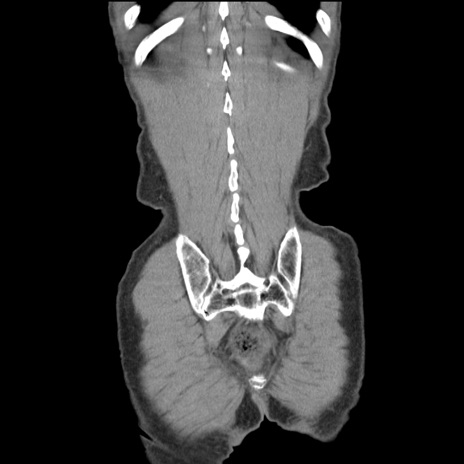

横断像